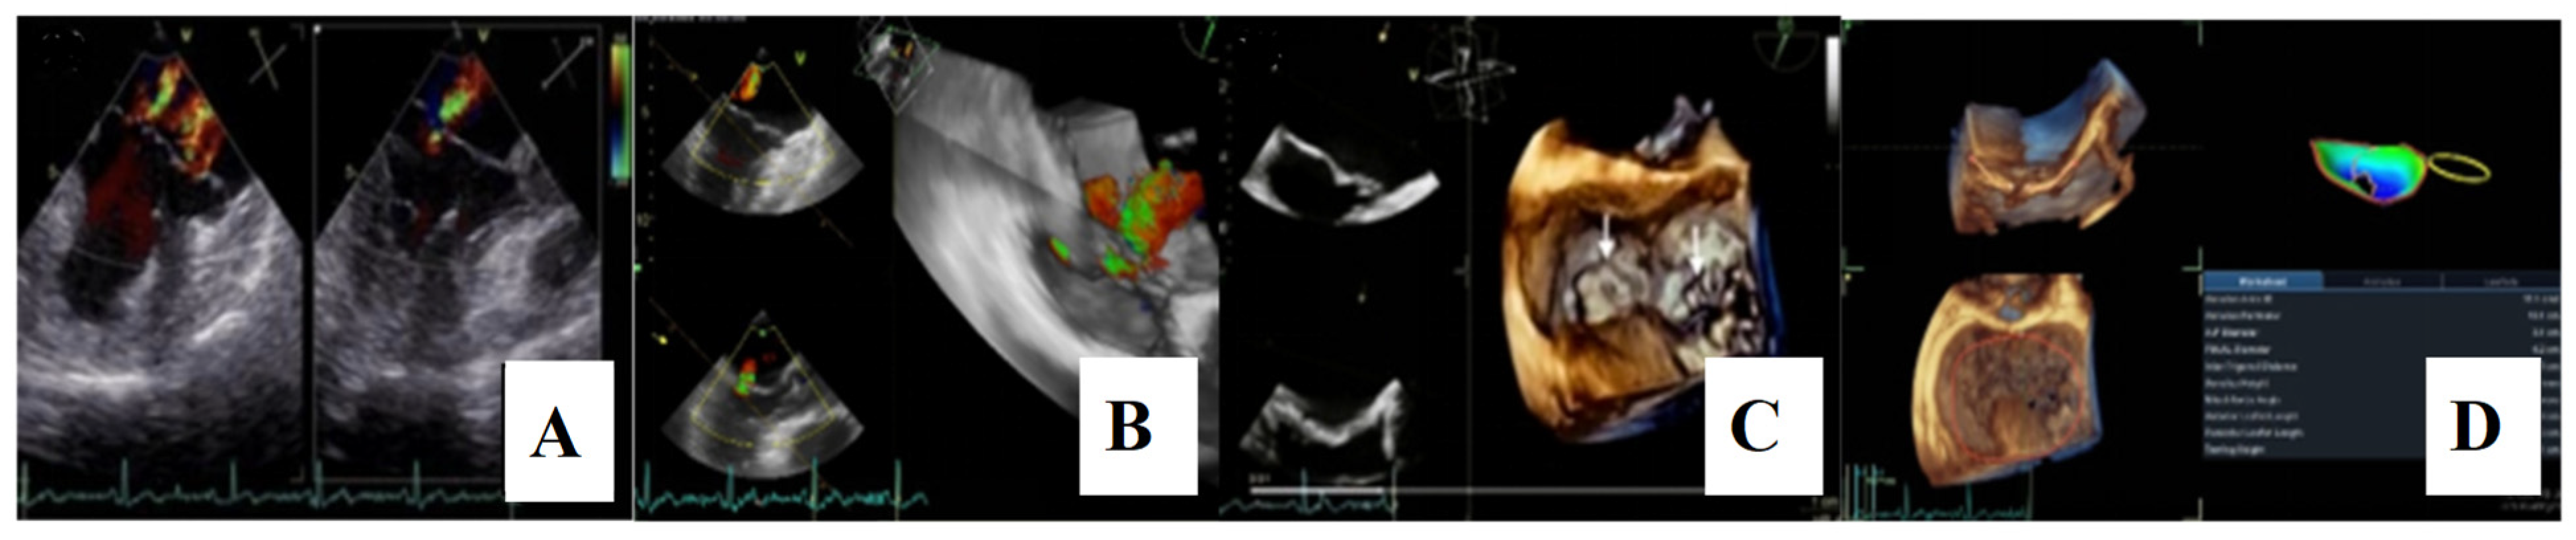

For a comprehensive morphological and functional evaluation of the mitral valve, transesophageal echocardiography was performed. Three-dimensional imaging provided an “en face” view of the mitral leaflets, which confirmed the previous diagnosis of bileaflet mitral valve prolapse involving scallops A1, A2, A3 and P1, P2, P3. Severe mitral regurgitation and moderate tricuspid regurgitation were also documented (Figure 6A–D).

Figure 6.

(A,B)—Transoesophageal echocardiography (TEE) showing severe mitral regurgitation. (C,D)—TEE 3D view, displaying bileaflet prolapse and mitral annular enlargement. Mitral valve apparatus geometry and mitral valve dynamics were evaluated using EchoPAC software version BT12.